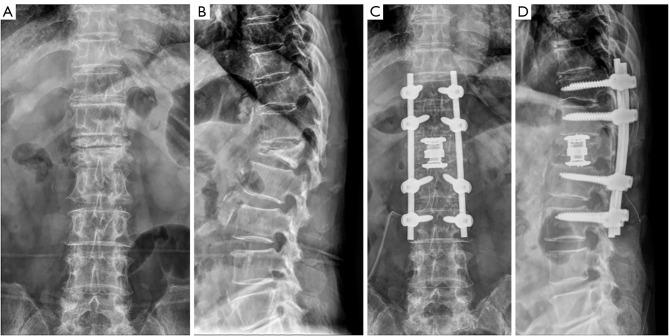

As a surgical treatment method for KD, we performed bone substitute packing via small pedicle holes with a posterior instrumented fusion. Ten consecutive patients underwent surgery for KD. Clinical outcomes and radiologic parameters were evaluated pre- and post-operatively.

The average operation time was 150.5±19.64 min with a mean estimated blood loss of 252±173.32 mL. The mean Visual Analog Scale (VAS) score for back pain was reduced from preoperative 8.7±0.82 to 2.8±1.14 (P<0.001), and the mean Oswestry Disability Index (ODI) score improved from 30.6±3.2 preoperatively to 11.6±4.81 (P<0.001) at the final follow-up. The sagittal Cobb angles decreased from 23.19±9.52 degrees preoperatively to 11.59±10.06 degrees (P<0.001) immediately after surgery, and 13.31±10.43 (P=0.002) degrees at the final follow-up. Except for 1 case of minor screw migration, there were no serious perioperative complications.

Transpedicular bone packing does not involve technically demanding procedures such as corrective osteotomy, vertebral column resection, and insertion of large metal cage. Therefore, it may be minimally invasive and reproducible surgical option.